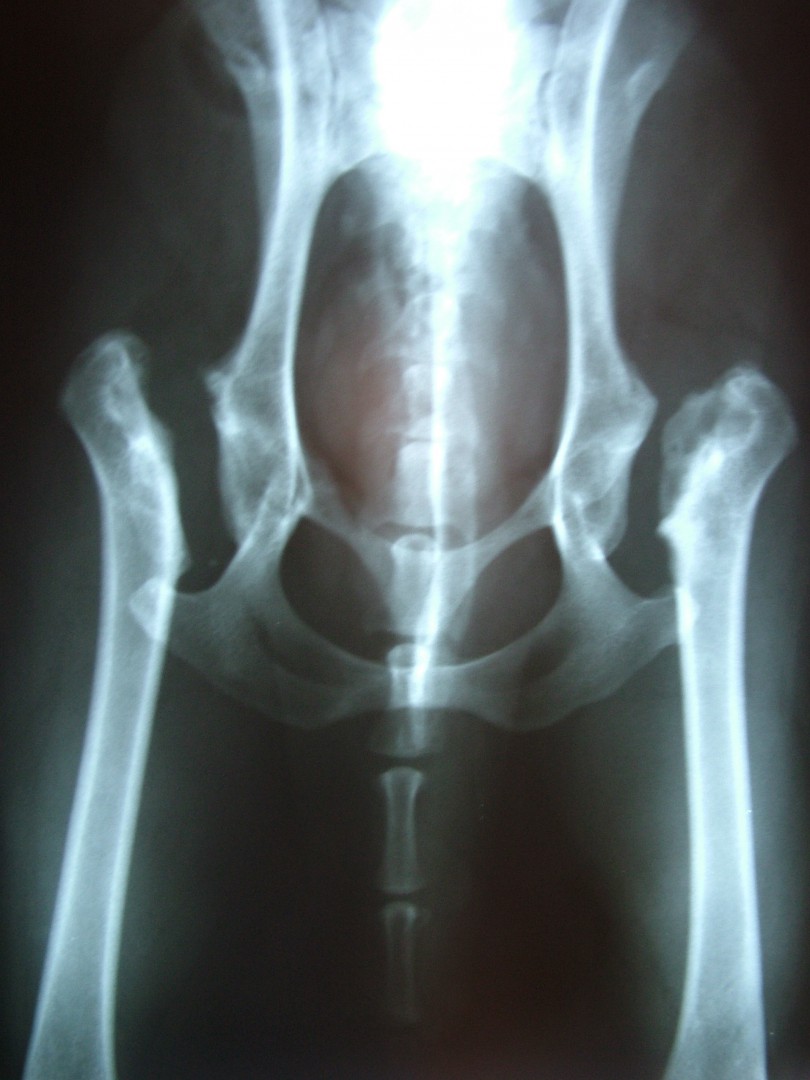

A felvételen a combcsontfej csontos szerkezetének felbomlása, sok esetben a combcsontfej beroppanása látható.

Legg-Perthes kór - Műtét

A röntgen felvétellel egyértelműen diagnosztizált betegség műtéti ellátást igényel. A beavatkozás során az elhalt combcsontfejet eltávolítjuk, megszűntetve az ízületi fájdalmat. A gyógyulási folyamat során a csípőízület helyén egy laza kötőszövetes kapcsolat alakul ki (álízület, pseudoarticulatio), mely fájdalommentes mozgást biztosít a medencecsont és a combcsont között.